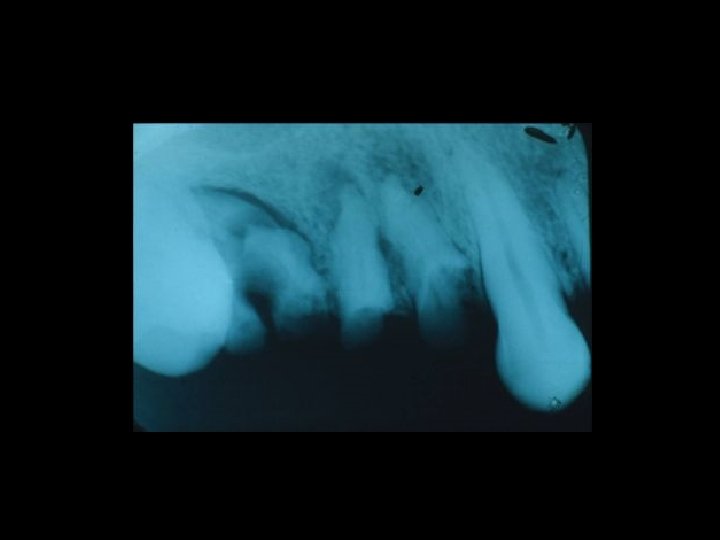

Responsabilità professionale dell’Odontoiatra La diagnosi Ø Messa in atto di interventi conosciuti e di provata esperienza Ø Atti ed omissioni Ø Nesso tra danno e intervento Ø

Il contenzioso PRINCIPALI AMBITI Ø Ø Ø La diagnosi La chirurgia orale La terapia conservativa Il trattamento delle anomalie dento-scheletriche La riabilitazione protesica